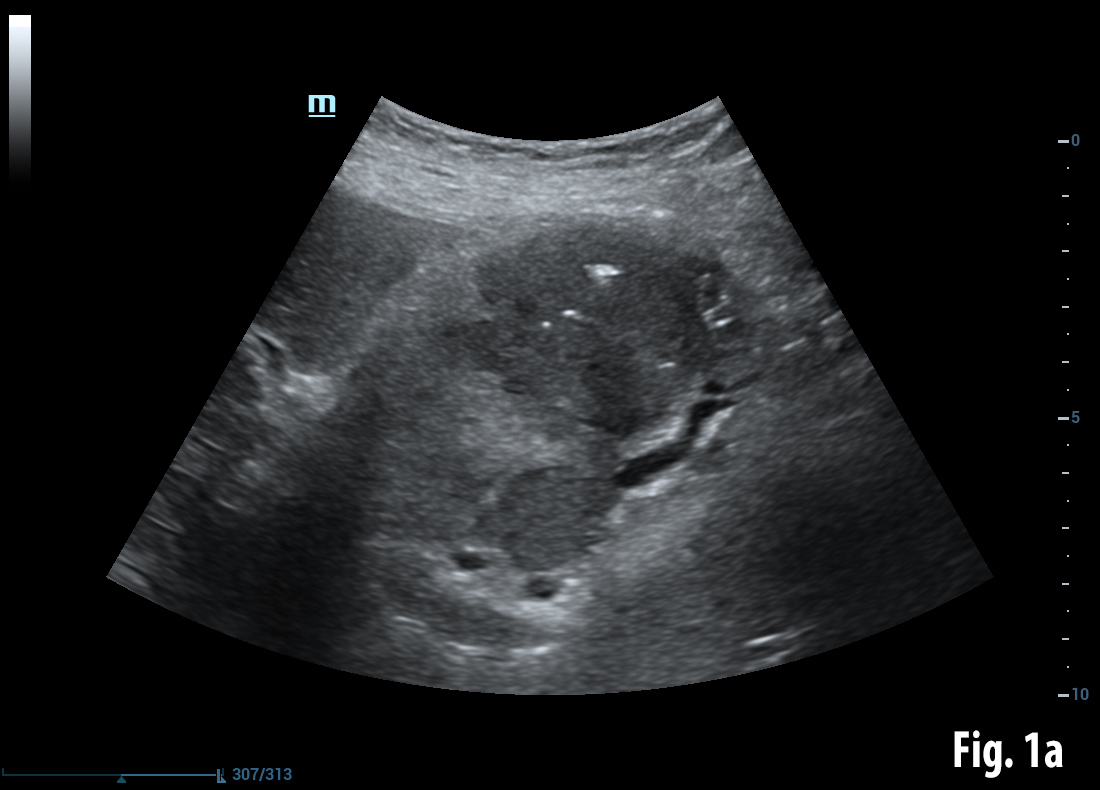

Conventional B-mode ultrasound revealed a mass lesion in the gallbladder region (a) and air bubbles within the liver (aerobilia) (b). Contrast enhanced ultrasound showed arterial enhancement as a sign of neoplasia (c). Endoscopy revealed a gallstone in the duodenal bulb (d). Elastography showed stiff tissue (blue) supportive of neoplasia (e). Details of elastography are explained in the EFSUMB guidelines on elastography [(1, 2)].

![Bouveret syndrome</br> [Apr 2016]](http://s834315022.websitehome.co.uk/wp-content/uploads/2020/11/cotm_april2016-fig1a.jpg)